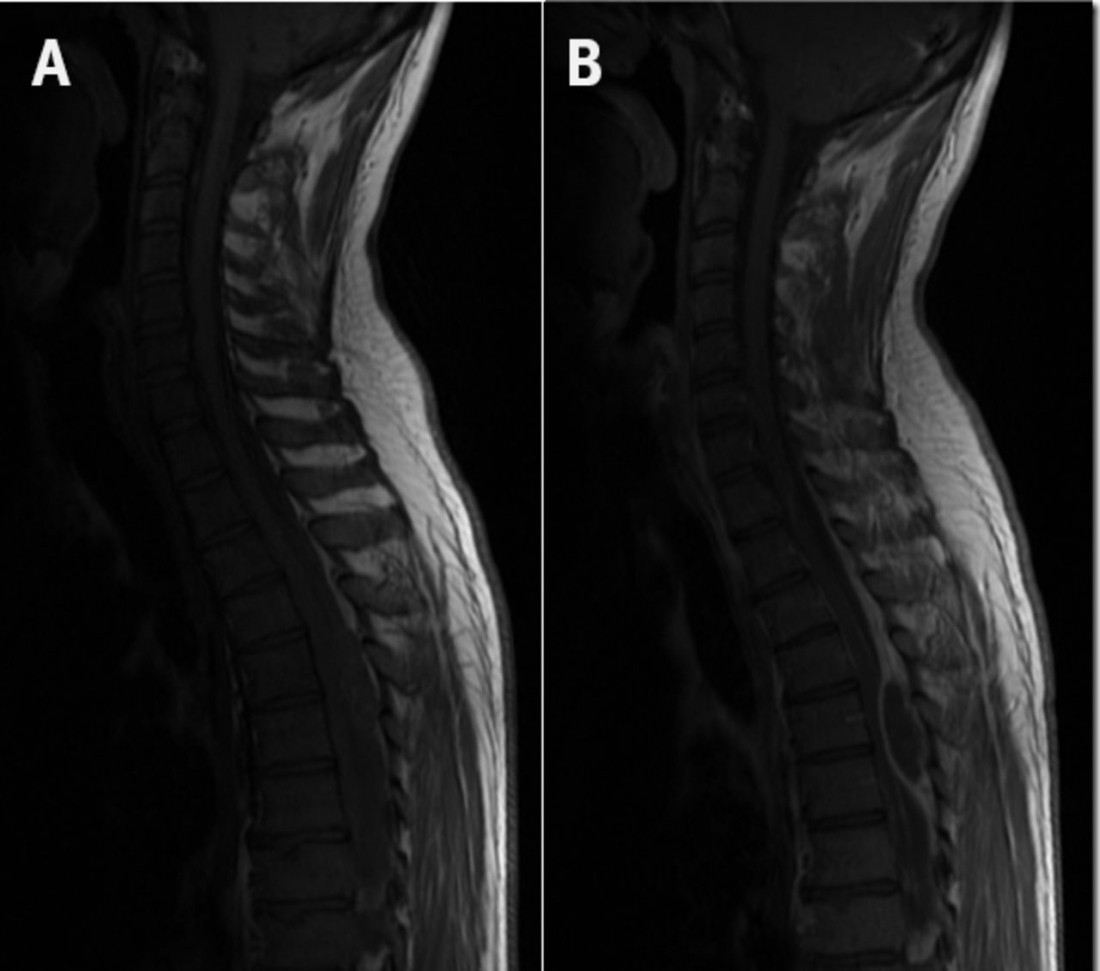

МРТ показала дисцит, деструктивный остеомиелит Th12 и L1, а также эпидуральный абсцесс (Рис. 1C). Срочно выполнена хирургическая декомпрессия, двусторонняя ламинэктомия и дискэктомия с дренированием поясничного абсцесса. После длительного периода реабилитации пациент почти полностью восстановился.

Рисунок 1. A и B. КТ органов брюшной полости при поступлении разрушение передней поверхности тела позвонка L1 (пунктирная черная стрелка), рядом – тромбы в НПВ (белые стрелки) и абсцессы поясничных мышц (черные стрелки)

C. МРТ после 2 недель госпитализации (Т1-изображения в режиме TSE с подавлением сигнала от жировой ткани): усиление сигнала от тел позвонков T12-L2 (черные стрелки) и эпидуральный абсцесс (белые стрелки).